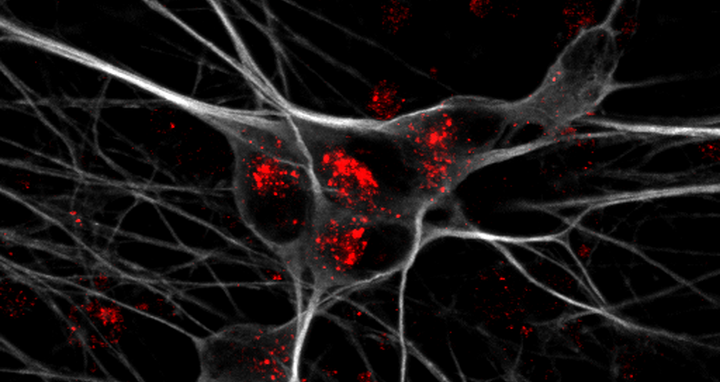

Detection of mitochondria (red) in cell body and neurites of iPSC-derived human neurons (green).

Detection of mitochondria (red) in cell body and neurites of iPSC-derived human neurons (green). Photo: Anna K Greda, Universität Aarhus